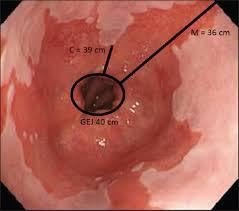

- Nội soi thực quản (dùng một ống mềm dễ uốn cong để nhìn vào thực quản): nội soi thực quản là một cách để kiểm tra trực quan bên trong thực quản và dạ dày của bạn. Trong quá trình nội soi, người tư vấn luồn một ống mỏng, mềm, dễ uốn cong có gắn đèn và một camera xuống cổ họng của bạn. Bác sĩ cũng có thể dùng nội soi thực quản để lấy mẫu sinh thiết cho các xét nghiệm chuyên sâu. Nội soi có giá trị trong việc tìm các biến chứng của bệnh như thực quản Barrett.

- Các thay đổi tiền ung thư ở thực quản (thực quản Barrett): ở thực quản Barrett, mô lót phần dưới thực quản bị thay đổi, kèm theo đó là gia tăng nguy cơ mắc ung thư thực quản. Mặc dù khả năng tiến triển tới ung thư rất thấp, người tư vấn vẫn sẽ cho làm nội soi thực quản để tìm các dấu hiệu cảnh báo ung thư thực quản sớm.